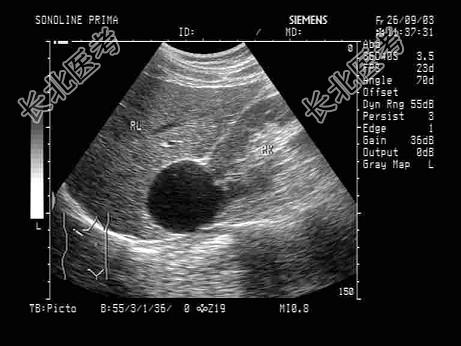

- 单项选择题根据声像图,下列最可能的诊断为   (   )

A、肾上腺囊肿

B、肾脓肿

C、嗜咯细胞瘤

D、肝囊肿

E、肾囊肿